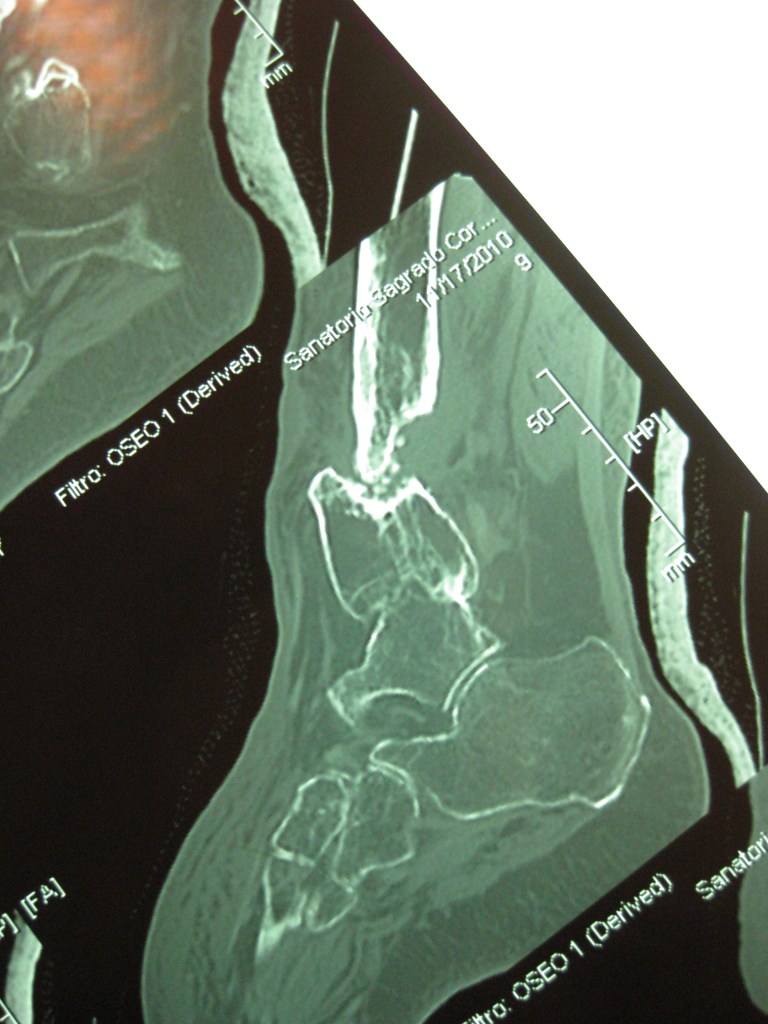

Infección y deformidad en tobillo y pie mas acortamiento óseo de pierna

Luego de varios años y cirugías sufridas por un accidente en moto, mi pie y pierna presentaban una gran deformidad asociada a una osteomielitis .

En mi provincia Chubut no podían tratarme más y solo me ofrecían la amputación

Tras viajar a BS AS y tener una consulta personal con el Dr Dratewka y Equipo en Cotram me realizaron estudios de imágenes y explicaron las posibilidades de Reconstrucción y evitar así la amputación

No solo trataron mi infección sino que corrigieron mi pie y me alargaron la pierna para poder caminar sin dificultades